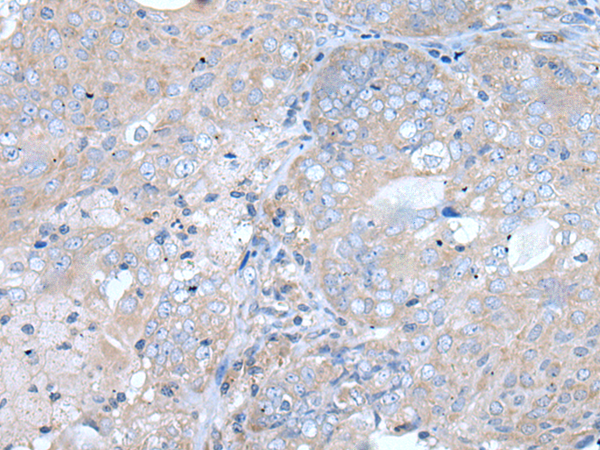

IHC positive control: |

Human lung cancer and human prostate cancer |

IHC Recommend dilution: |

25-100 |